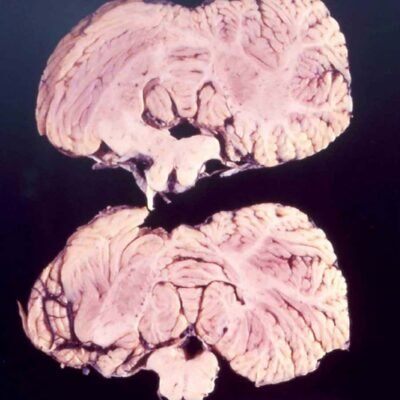

[ad_1] The cerebellum of a person affected by kuru Liberski PP (2013) A genetic study in an extraordinarily remote community in Papua New Guinea has